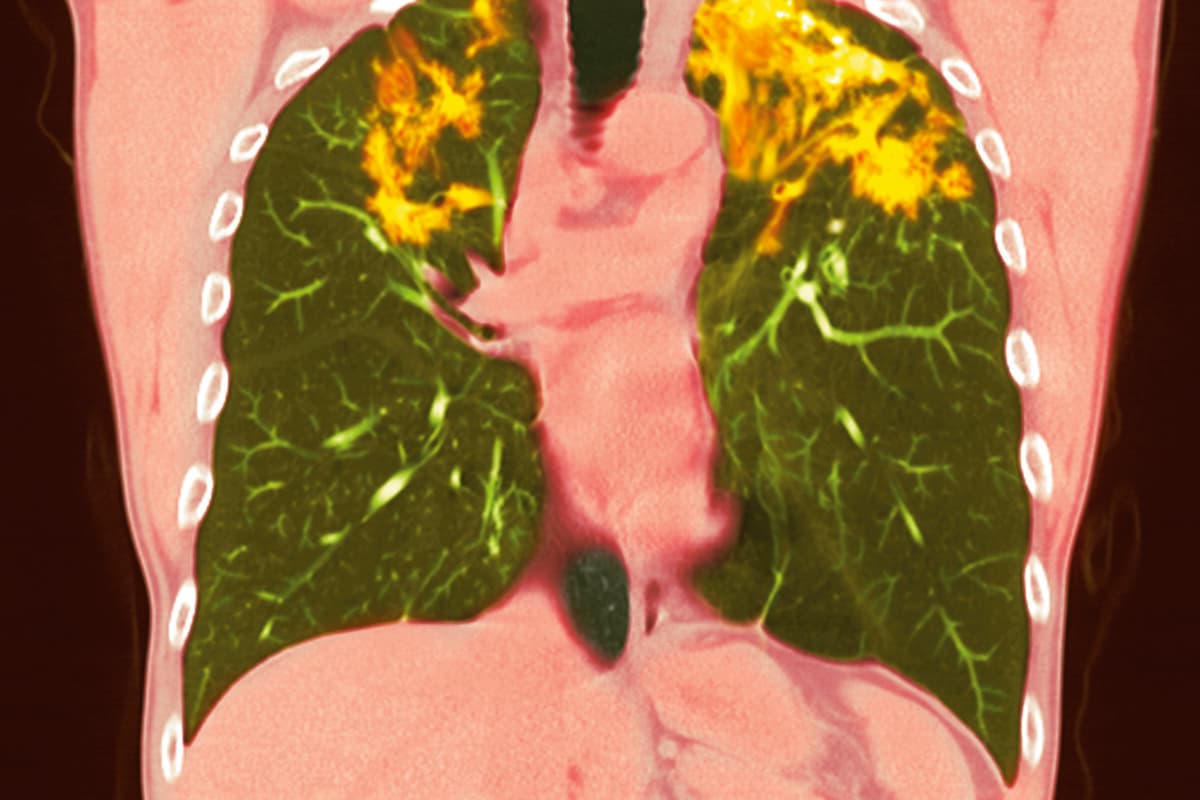

Diagnostisch zeigt eine hochauflösende CT bei SAPF

- Distorsionen der Bronchien,

- lineare Milchglastrübungen,

- grosse zystische Honigwaben und

- Traktionsbronchiektasen.

Die meisten fibrotischen Anomalien dabei in den oberen und mittleren Lungenbereichen auf. Das ist ähnlich wie bei der hypersensitiven Pneumonitis; bei dieser ist allerdings eine zentrilobuläre Verteilung üblich, während sich Noduli bei der SAPF vor allem bronchiovaskulär befinden. Mosaikmuster durch eine Ansammlung von Atemluft («air trapping») liegen bei SAPF eher selten vor.